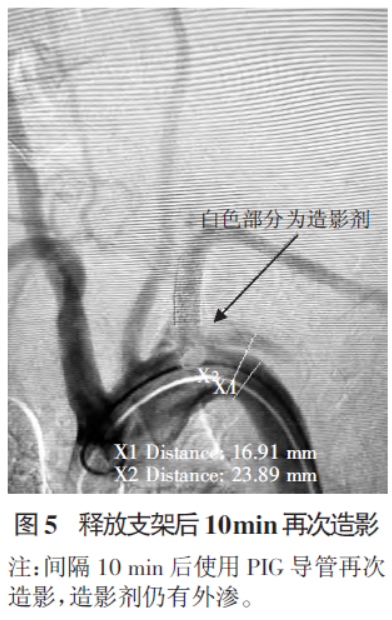

考虑形成锁骨下动脉-胸主动脉夹层,破口位置位于支架近端下缘。间隔10 min 后再次造影,仍有造影剂外渗至胸主动脉壁,见图5。

5.png